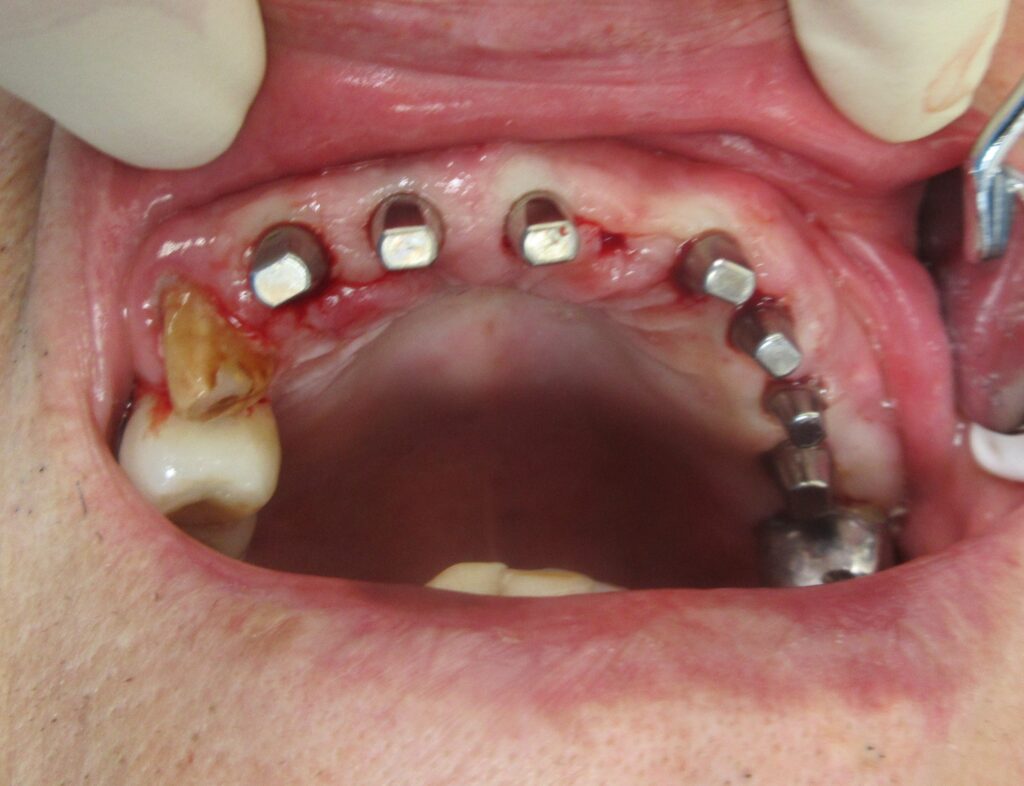

今回の患者様は、以前にもインプラントを植立された経験がある方で、今回もインプラント植立を希望されたので、右上1番目・2番目、左上1番目、2番目~6番目の合計7本の植立が決まりました。

開けた穴に、専用道具を使ってネジを締めるように長さ2センチ程のインプラントを骨に埋め込んでいきます。

続けて、その他の部位も同じ工程で植立を行いました。

インプラントオペでは、隣り合う歯にインプラントを植立する場合でも、複数本同時に進行することはせず1本ずつ同じ工程を繰り返して植立します。

しっかりとインプラント埋め込まれた後は、動揺がないか、噛んだ時に当たらないかなどを確認して、最後にパノラマ写真を撮影して今回のオペは終了となりました。